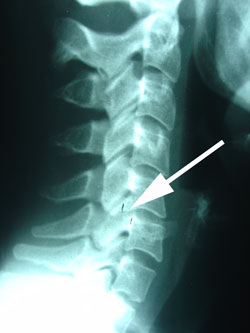

Cervical spine subluxations can irritate the nerves of the disc, facet joints, and spinal nerves leaving the spine to cause pain in the shoulders, neck, arm, and head (headache). At arrow, see the vertebra is moved backwards on the one below representing a subluxation.